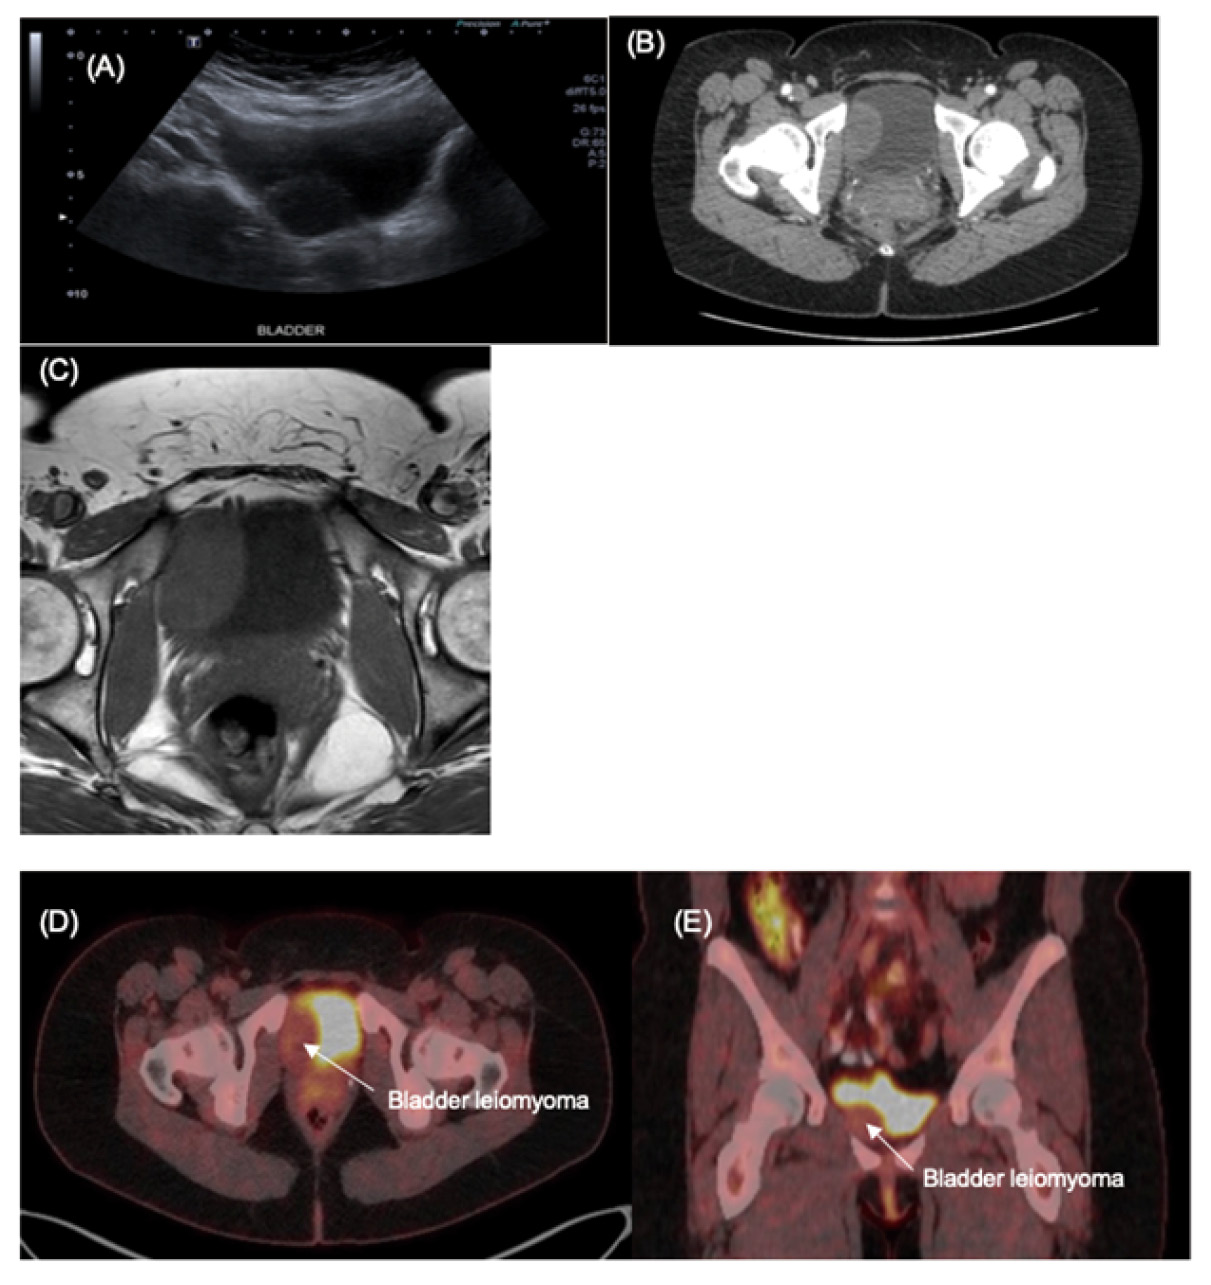

Urine culture and cytology confirmed no infection or malignant cells. Ultrasound demonstrated a hypoechoic lesion on the right anterior bladder wall, measuring 44 × 42 × 28 mm. CT showed a soft-tissue attenuation mass protruding into the bladder lumen, exhibiting equivocal mild lesional enhancement. MRI demonstrated a heterogenous bladder tumor appearing intramural, rather than intraluminal (Fig. 1). The mass was mobile on bimanual examination and cystoscopic evaluation visualized a large mass indenting the right bladder wall (Fig. 2). A transurethral resection biopsy was considered but not performed for the concern of spreading a malignant process.

Figure 1. (A) Sonographic appearance of hypoechoic mass arising within the bladder wall; (B) Axial CT demonstrating a smooth contour soft tissue density within the inferior bladder; (C) MRI T1 weighted axial image demonstrating that the lesion had similar intensity to muscle; (D) Axial FDG-PET/CT demonstrating mild FDG uptake in bladder lesion (SUVmax 3.2); (E) Corresponding Coronal FDG-PET/CT

Her case was reviewed at our institutional multi-disciplinary meeting, given concerns that it could represent a rare sarcomatous process. A FDG-PET CT was performed and low-grade FDG uptake (metabolic activity) was displayed with no avid nodal or distant metastatic disease (Fig. 1).